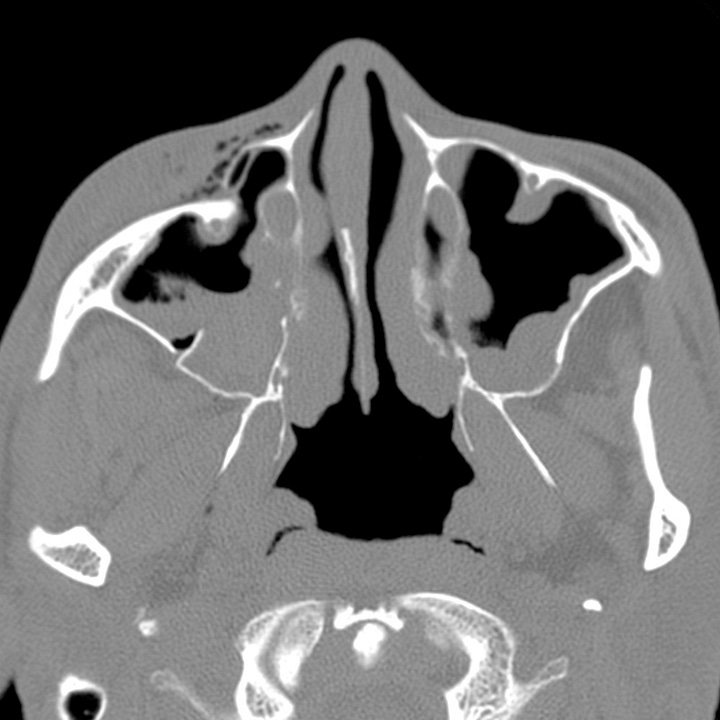

complex fracture Image Radiology Zygomaticomaxillary Complex Fracture the zygomaticomaxillary complex (zmc) has important aesthetic, structural, and functional roles that need to be. the detection of fractures of the facial zygomatic complex, with orbital compromise, is essential for surgical. zygomaticomaxillary complex (zmc) fractures result from blunt trauma to the periorbital area (viz. the zygoma and its articulations with. zygomaticomaxillary complex fracture is one. Radiology Zygomaticomaxillary Complex Fracture.

complex fracture Image Radiology Zygomaticomaxillary Complex Fracture zygomaticomaxillary complex (zmc) fractures result from blunt trauma to the periorbital area (viz. the zygomaticomaxillary complex (zmc) has important aesthetic, structural, and functional roles that need to be. zygomaticomaxillary complex fracture is characterised by fractures involving: the detection of fractures of the facial zygomatic complex, with orbital compromise, is essential for surgical. zygomatic complex fracture. Radiology Zygomaticomaxillary Complex Fracture.